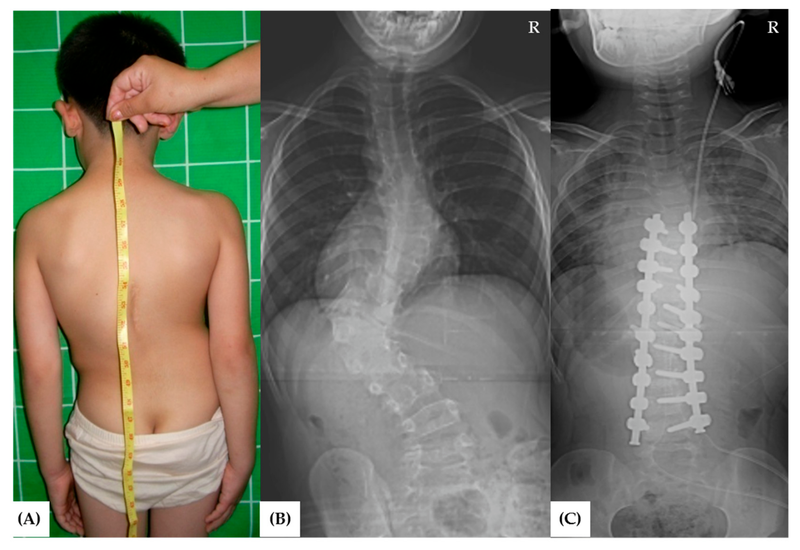

Để chẩn đoán chứng vẹo cột sống bẩm sinh, bác sĩ sẽ khám sức khỏe và khai thác bệnh sử đầy đủ cho bé. Bác sĩ cũng có thể yêu cầu chụp X-quang để xem xét kỹ hơn hình ảnh của phần cột sống bị ảnh hưởng trên phim.

Khi chứng vẹo cột sống bẩm sinh đủ nghiêm trọng để cần điều trị, trẻ thường cần phải phẫu thuật. Nẹp và các phương pháp điều trị không phẫu thuật khác thường không hiệu quả đối với chứng vẹo cột sống bẩm sinh. Điều trị phẫu thuật sẽ phụ thuộc vào độ tuổi và giai đoạn tăng trưởng của bé.

Phẫu thuật hợp nhất đốt sống là phương pháp điều trị phẫu thuật phổ biến nhất cho chứng vẹo cột sống nặng ở thanh thiếu niên. Phẫu thuật làm thẳng cột sống và củng cố xương để nó sẽ không còn cong bất thường nữa. Trong 6 đến 12 tháng sau khi phẫu thuật hợp nhất đốt sống, cột sống sẽ liền lại theo cách tương tự như cách xương gãy lành lại. Con bạn có thể cần phải đeo nẹp trong thời gian này.